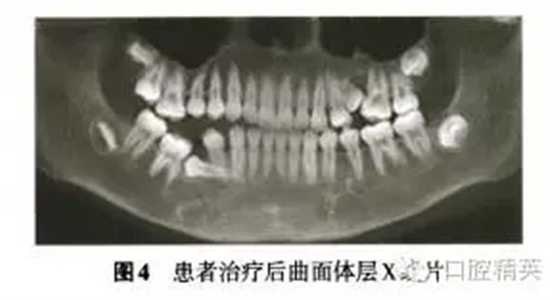

診斷:安氏Ⅲ類亞類錯牙合畸形,5V、5V阻生。治療方案:①拔除V,V,清理V囊腔;②牽引5至正常牙列;③試牽引5,不排除牽引失敗的可能;④使用種植體支抗防止鄰牙壓低和對牙合牙伸長;⑤糾正右側(cè)后牙開牙合,若654粘連導(dǎo)致正畸治療無效,則需調(diào)整治療方案。拔除埋伏乳磨牙時(shí),錐形束CT確認(rèn)下頜神經(jīng)管位于阻生V根分叉下方(圖3),5牙根位于43舌側(cè)。手術(shù)順利拔除埋伏阻生的V、V,8個(gè)月后曲面體層x線片示牙槽骨愈合良好,可見4顆第三磨牙牙胚(圖4)。但患者家長放棄牽引治療。